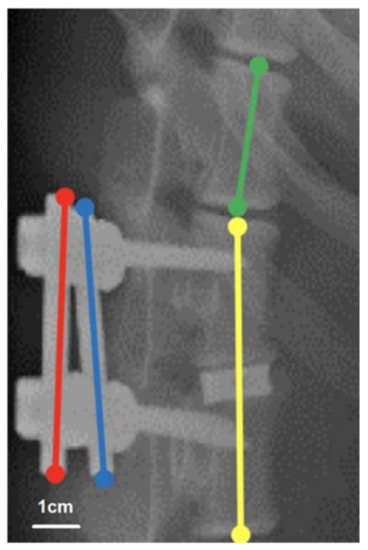

To evaluate the morphology of the implant site before euthanasia, we generated plain radiographs immediately and at 1, 3, and 6 months after surgery. To evaluate cage fusion, we measured the lengths of the radiolucent lines at the cranial and caudal vertebrae–implant/graft interfaces and the total lengths of these interfaces on lateral radiographs [26]. Radiographic grading was performed by dividing the length of the radiolucent lines by the total length of the vertebrae–implant/graft interface. The radiolucent lines at the vertebrae–implant/graft interfaces represented three states of healing and were categorized according to their relative percentages into the following categories to represent the three states: >50% radiolucent lines, ≤50% radiolucent lines, and absence of radiolucent lines. To evaluate cage subsidence, we measured the fusion segment lengths on lateral radiographs at each time point and adjusted the measured lengths on the basis of the upper vertebral height for natural bone growth (Figure 2). The length of the connecting rods was 5 cm, which was half the sum of the lengths of the bilateral rods (red and blue lines in Figure 2). The vertebral growth ratio (VGR) is the ratio of the upper adjacent vertebral body length (green line in Figure 2) to the lower adjacent vertebral body length (yellow line in Figure 2) at a given time point on the day of the operation. Furthermore, the fusion segment length is the ratio of the length of the fusion vertebrae and interbody cage (yellow line in Figure 2) to the VGR multiplied by 5 cm (i.e., the length of the connecting rod).

Figure 2. Assessment of fusion segment length. With a real connecting rod length of 5 cm, the sum of the measured length of the bilateral rods (red and blue line) divided by 2 is regarded as the measured connecting rod length, which should be 5 cm. For adjusting the bone growth of the vertebra, the vertebral growth ratio (VGR) is defined as the upper adjacent vertebral body length (green line) divided by the lower adjacent vertebral body length (yellow line) at a given time point on the day of the operation. The fusion segment length is defined as the length of the fusion vertebrae and interbody cage (yellow line) divided by the length of the measured connecting rod × 5 cm × VGR.